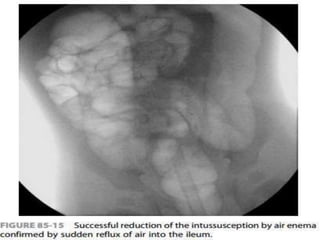

Air should flow freely from the cecum into the

distal small bowel loops to signify complete

reduction

Passage of air into the terminal ileum

without complete reduction of the ileocolic

intussusception

Air should flowfreely from the cecum into the distal small bowel loops to signify complete reduction Keep air pressure below a maximum limit of 120 mm Hg to avoid the risk of perforation